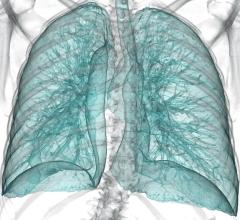

Primordial announced the debut of its application for lung cancer screening program management and its customer implementation at Lahey Hospital & Medical Center (LHMC), an ACR Designated Lung Cancer Screening Center.

Manufacturers have introduced hybrid imaging systems that combine positron emission tomography (PET) with magnetic resonance imaging (MRI). The purported benefit is improved detail in organ and soft-tissue images without the ionizing radiation inherent with systems that combine PET with computed tomography (CT), the gold-standard hybrid imaging modality.